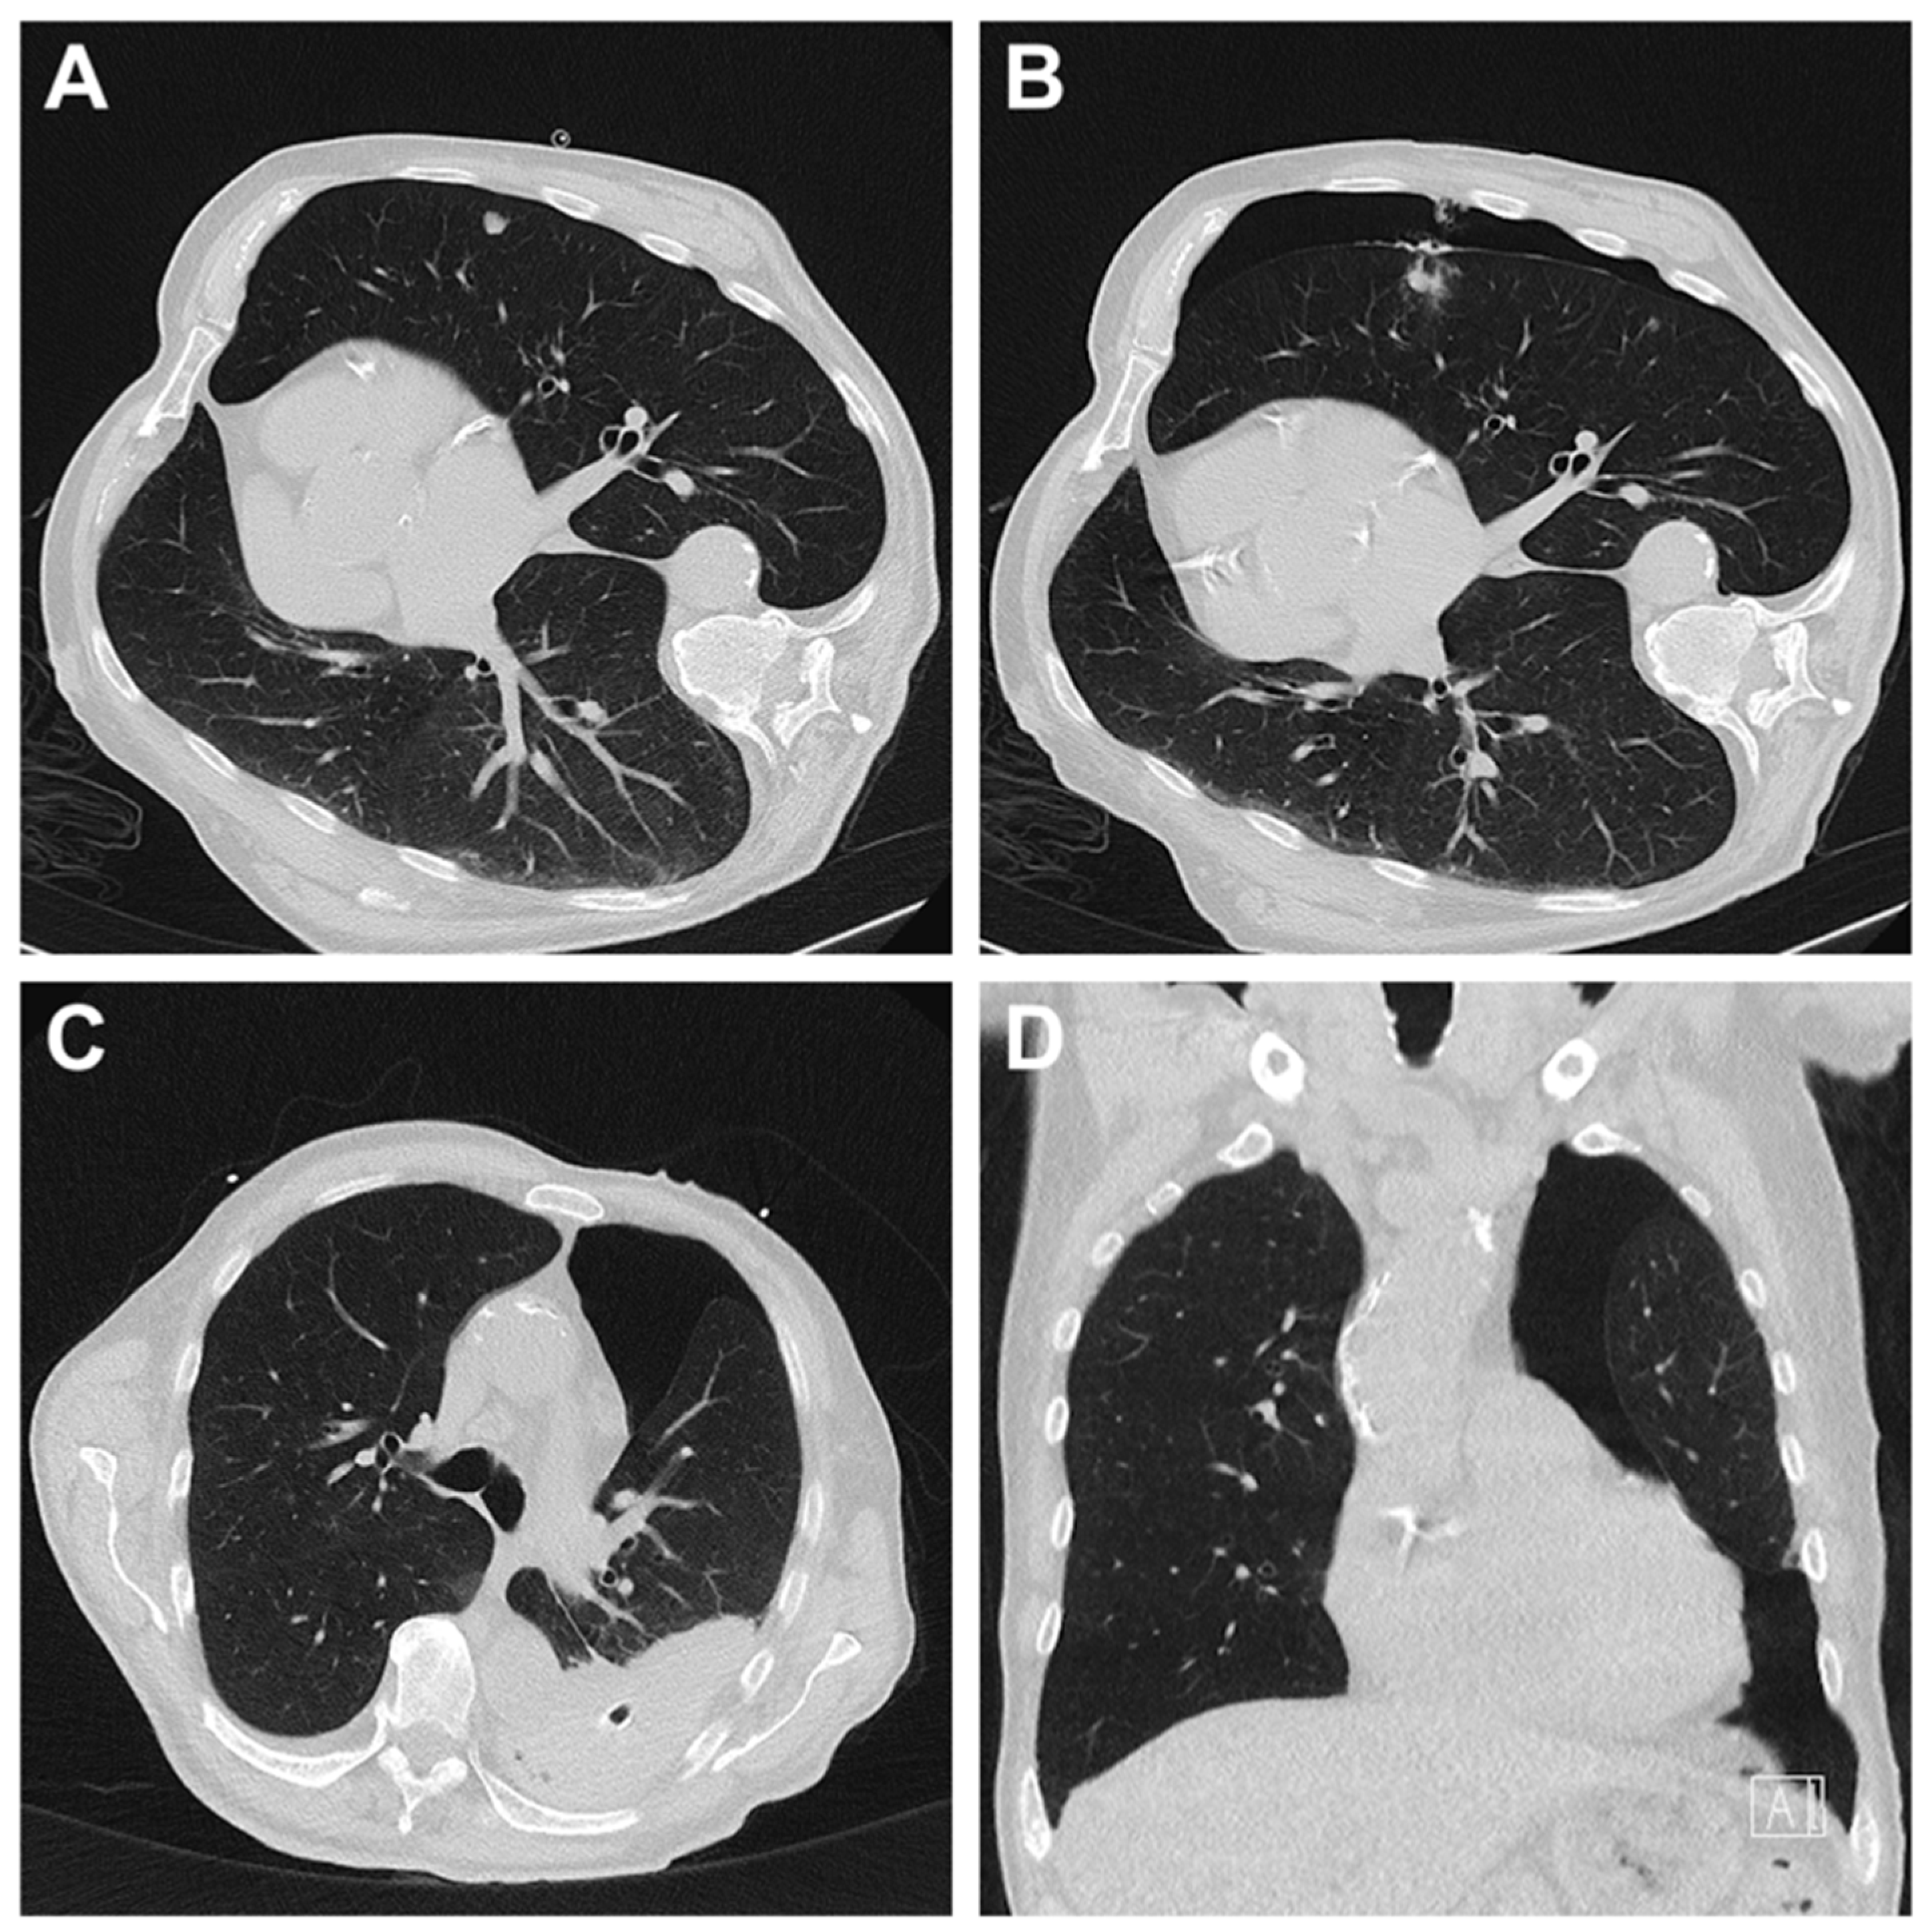

3.3. Radiation Dose for CT-Guided Biopsies

3.4. Complications